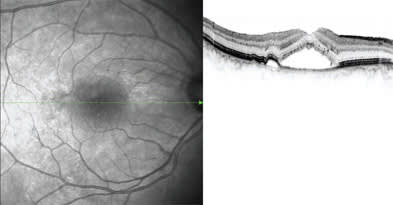

Figure 1. The Spectralis HRA+OCT captures images simultaneously. Here, a diagnosis of central serous retinopathy (CSR) is shown. The image on the left shows the infrared view through the HRA2 SLO. The image on the right shows the OCT cut at the location of the vertical green line on the HRA2 SLO.

With the Spectralis, cross-sectional images are simultaneously registered to any of the following reference images: FA, indocyanine green angiography (ICG), autofluorescence, red-free or infrared; and dual-beam imaging captures the reference scan and cross section simultaneously, creating an accurate and reliable reference point (Figures 1-3). Dr. Bartsch explains that while he and his colleagues knew that spectral-domain OCT was going to significantly improve diagnostic capability in comparison to time-domain OCT, they did not foresee how beneficial some of the other assets of the Spectralis would be. "For instance, we can get a side-by-side infrared image and OCT image of the exact same spot on the retina," says Dr. Bartsch. "That's possible with auto-fluorescence, as well, so we can get an image and pinpoint the pathology and then view the OCT image that corresponds directly with that image." Dr. Bartsch says that another useful feature is the volume scan capability. "There are times where you might be looking at an image, and you might see a very small abnormality, and wonder if that abnormality is significant, such as when you see a tiny spot of blood in a patient with non-exudative AMD," he explains.